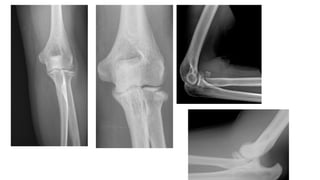

INVESTIGATIONS

• X-RAY

• Anteroposterior, lateral, and oblique Views.

RADIOGRAPHIC EVALUATION

• Anteroposterior and lateral radiographs.

• GREENSPAN VIEW / RADIOCAPITELLAR VIEW-

forearm in neural rota)on and the radiographic

beam angled 45 degrees chephalad.

• It provides visualisa)on of the radio capitellar

ar)cula)on.